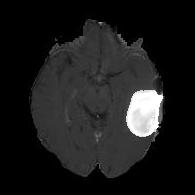

We argue that the sub-optimal paradigm of processing different abstractions within a single CNN pipeline can be remedied through the effective processing of information in a structured manner. Consequently, we devise strategies for disentangling the edge and texture information within a single training pipeline. Figure 2 illustrates how our proposed module, dubbed EG-CNN, can be paired with any existing CNN encoder-decoder to improve segmentation quality near intensity edges. We have applied our EG-CNN to the tasks of brain and liver tumor segmentation in medical images (Figure 3).

(1) Brain MR (2) Liver MR (3) Liver CT (4) Lung CT